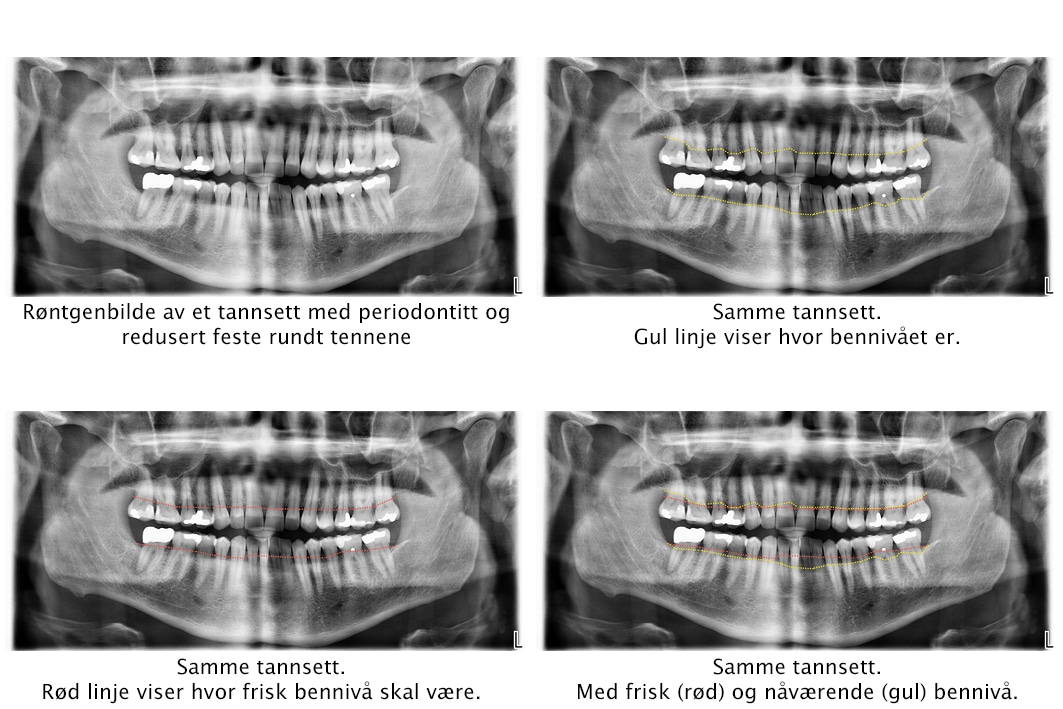

I hovedsak er det to undersøkelser som kan gi en indikasjon på sykdommen; klinisk og røntgen.

Ved klinisk undersøkelse måler vi avstanden mellom tannkjøttsranden og kjevebensfeste. Normalt skal denne avstanden være 2-3mm, er den over 4 mm er dette en antydning på tannkjøttsykdom. Dette kalles for lommemåling. En klinisk undersøkelse med lommemåling vil kunne gi en indikasjon på hvor alvorlig tilstanden er, og ikke minst hvilke behandlingsmetoder som burde benyttes.